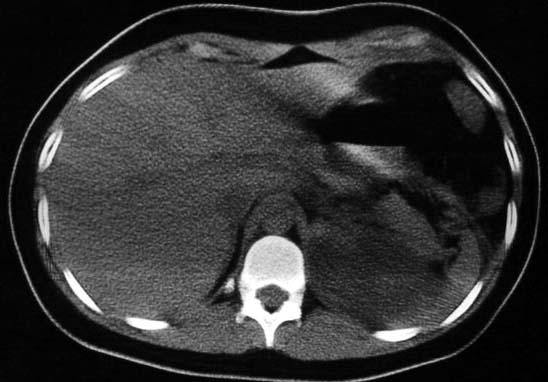

标题: CT5517:女性、24岁,反复胸痛、气促不能平卧半月。 [打印本页]

标题: CT5517:女性、24岁,反复胸痛、气促不能平卧半月。

左侧气液腔与胃腔影相连,考虑膈疝。钡餐检查有助于诊断。

我看这是膈疝,在纵隔窗第六\\七幅图像上可见胃粘膜影,再者可见两个腔影,这在液气胸是不会有的.

支持膈疝,纵隔窗内可见消化道的内容物。

谨慎!喝钡透视一下吧。冒然报一液气胸,临床再穿刺引流结果把胃戳个大洞就麻烦了!

不排除先天畸形,1.左肺支气管肺囊肿,左肺发育不良,2.左纵隔先天畸形?3.胸腔胃?